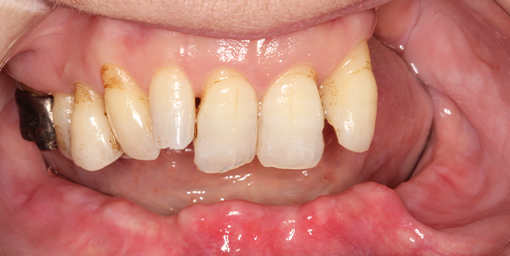

取り外しの入れ歯でなくしっかり食事を楽しみたい【オールオン5・インプラント・虫歯治療(保険診療)】